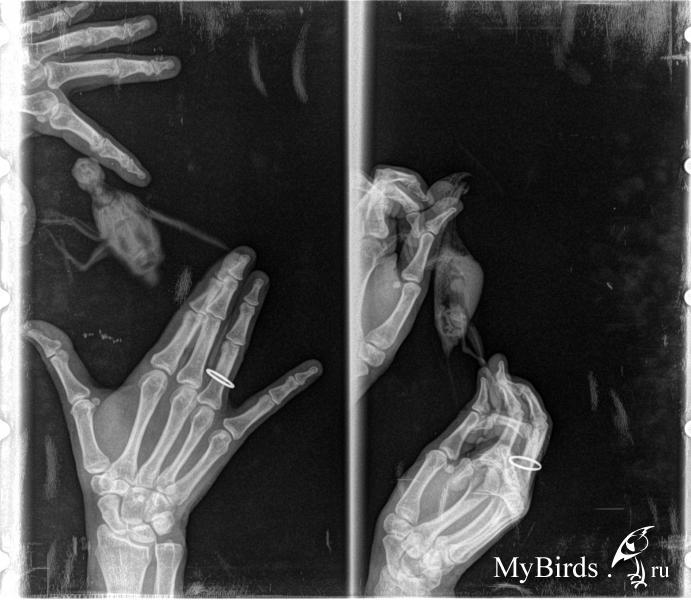

Сходили сегодня на прием, сделали. рентген. Поставили предварительный диагноз пневмония. Сдали анализы на исследование биоматериала методом ПЦР и посев на дерматофиты. Сказали, что если пневмония вызвана аспергелезом, то это неизлечимо. Так ли это?

Напишите Зосе, чтобы зашла в вашу тему и посмотрела снимок. Еще на какой нибудь ресурс выложите в нормальном (не ужатом) качестве снимок, а то этот очень уж маленький.

По вашим снимкам я даже с лупой не вижу ничего, уж очень меленько все. Может Маша(ЭКВИ) увидит, у неё глазки получше моих.